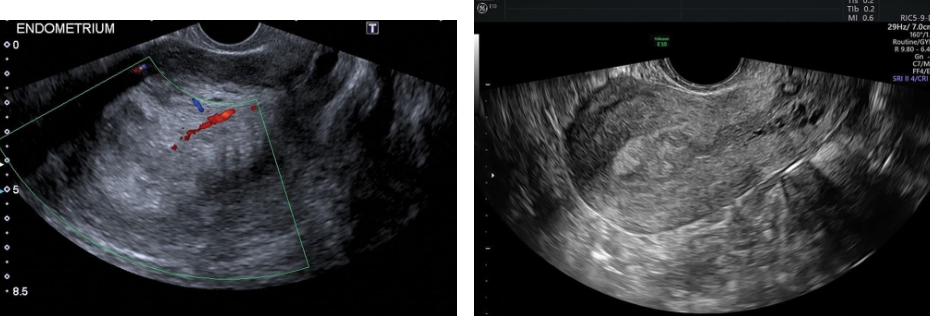

Sonographic Findings

Sonographically, polyps appear toward the end of the luteal phase and are represented by a

hypoechoic or isoechoic region within the hyperechoic endometrium.

They initially may appear as nonspecific echogenic endometrial thickening.

The polyp may be diffuse or focal and may also appear as a round echogenic mass within the

endometrial cavity.

Cystic areas representing histologically dilated glands may be seen within a polyp.

A feeding artery in the pedicle may be identified with color Doppler.

Individual polyps are better visualized when outlined by intracavitary fluid.

Sonohysterography is a valuable technique when transvaginal sonography is unable to differentiate an

endometrial polyp from a submucosal leiomyoma. Color Doppler sonohysterography can be

particularly useful in discriminating polyps from submucosal myomas based on the presentation of

feeding vessels. Polyps present most often with one primary feeding vessel, whereas myomas typically

have multiple microvessels arising from the inner myometrium.

Endometrial Polyps